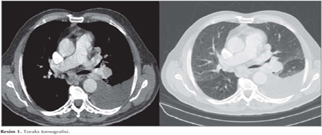

Yetmi? iki ya??nda, erkek hasta, May?s 2013 tarihinde sol yan a?r?s? ve hemoptizi ?ikayetiyle klini?imize ba?vurdu. Mevcut ?ikayetleri iki ay i?inde artan hastada d?? merkezde ?ekilen toraks ve abdomen tomografilerinde mediastinal lenfadenopatiler, sol akci?erde masif plevral ef?zyon i?inde ve parankimde multipl metastatik lezyonlar, sol b?brekte 126 mm nekrotik, egzofitik renal sinusa invazyon yapm?? malign kitle lezyonu ile sol surrenal lojda 24 mm'lik heterojen kitlesel lezyon saptand? (Resim 1). Hastan?n al?nan plevral s?v?s? malign sitolojiyle uyumlu olarak gelmi?. Hastaya sol b?brekten yap?lan tru-cut biyopsi sonucunda renal h?creli karsinom (?effaf h?creli tip ile uyumlu) saptanm??t?r. Hastaya yap?lan fiberoptik bronkoskopide sa? intermediyer bron?u tama yak?n t?kayan lezyon g?r?lmesi nedeniyle giri?imsel bronkoskopi yap?lmak ?zere hastanemize y?nlendirilmi?tir. Hastaya genel anestezi alt?nda rijid bronkoskop ile alt lob apikal segmentten kaynaklanan ve intermediyer bron?u tama yak?n t?kayan polipoid EBL 60 watt argon ile koag?le edilerek rijid forcepsle ??kar?ld? ve i?lem sonras? orta ve alt lob segmentlerinde tam a??kl?k sa?land? (Resim 2,3). Lezyondan al?nan biyopsi sonucu renal h?creli karsinom ile uyumlu olarak geldi (Resim 4).